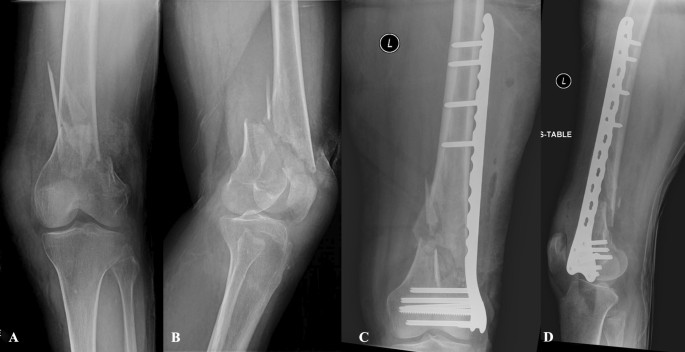

• Knee fractures – involving the patella (kneecap), tibial plateau, or distal femur.

• Tibia and fibula fractures – injuries to the shinbone and outer leg bone, ranging from simple to complex fractures.